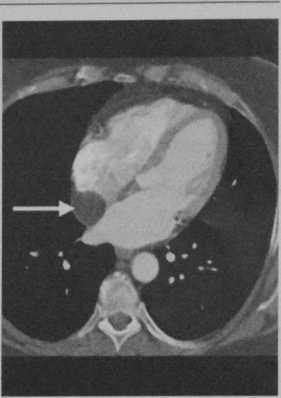

Внутрипредсердная липома у мужчины 54 лет (случайная находка). Аксиальная контрастно-усиленная КТ демонстрирует образование пониженной плотности с растворением жировой ткани [стрелка).